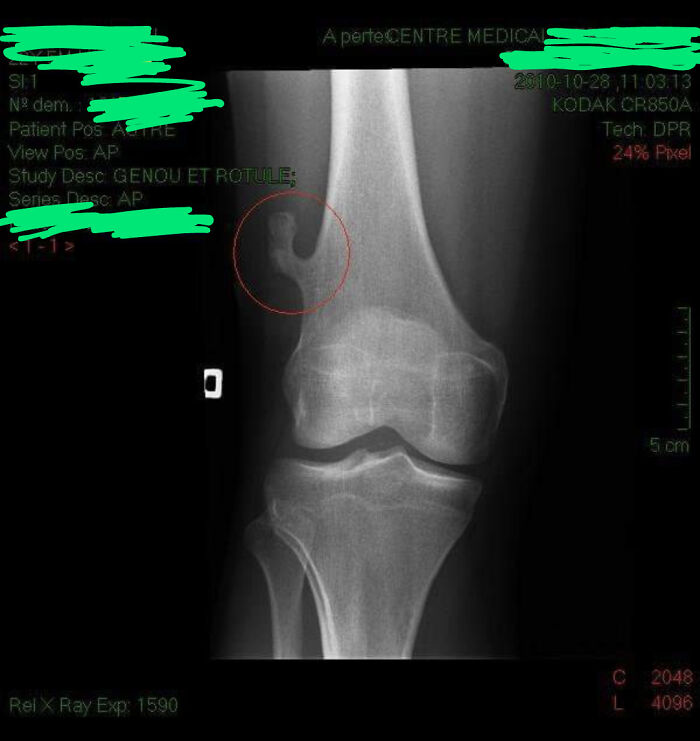

I Just Found My X-Ray From 2010. It Shows An Abnormal Bone Growth On My Right Femur That Has Since Been Surgically Removed